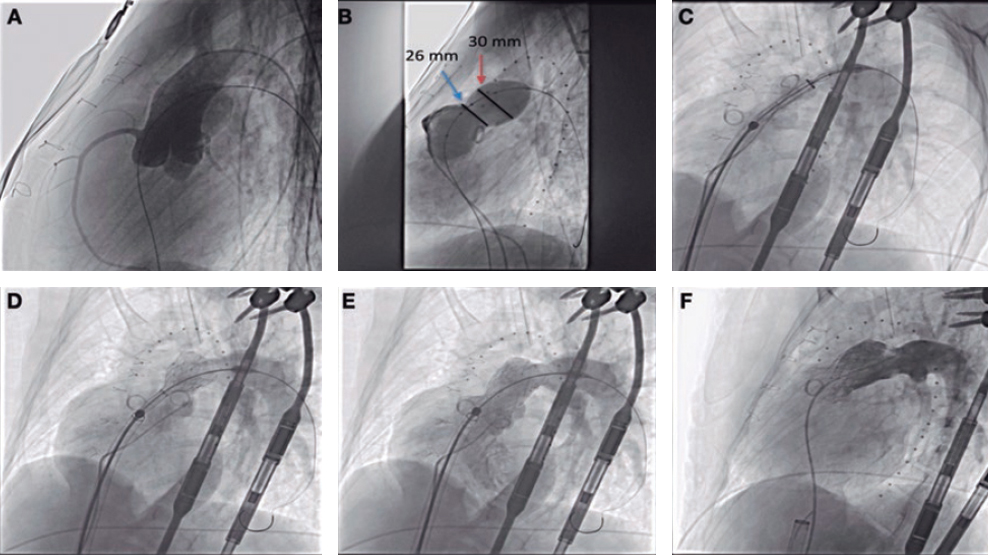

Ectasia and great proximal-distal diameter mistmatch at the lesion were the main indication for the use of this stent, in 72.6% of the lesions, with a mean vessel reference diameter of 4.1 mm ± 0.8 mm. A certain size was required to use this type of stent. The percutaneous coronary interventional on a bifurcation was the second most common indication, in 27.4% of the patients (2 of them on the LMCA). The most common type of bifurcation according to the Medina classification was 1-1-0, in 9 cases (52.9%). The secondary branch was damaged in 17% of the patients. The provisional stenting technique was the most widely used in 15 cases (88.2% of bifurcations) re-crossing to the secondary branch in 9 of them (60%). The dilatation of the secondary branch only occurred in 7 patients and only in the other 2 stents were implanted: one in a 0-1-1 bifurcation according to the Medina classification (minicrash technique) and the other in a 1-1-1 bifurcation according to this classification (TAP technique [T-and protrusion technique]). In both cases the STENTYS Xposition S stent was implanted in the main vessel and a non-self-apposing stent in the secondary branch (figure 1).

Figure 1. A: lesion with significant thrombotic load in the mid right coronary artery, which remains after thrombus aspiration. B: 3.5-4.5 mm × 27 mm Xposition S direct stent implantation. C: final angiographic result. D: significant stenosis in distal left main coronary artery. E: 3-3.5 mm × 27 mm Xposition S stent implantation from the proximal left main coronary artery to the left anterior descending coronary artery. F: angiographic result after postdilatation.